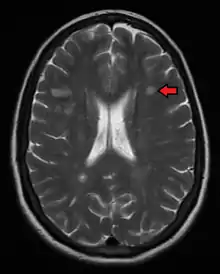

Magnetic resonance imaging (MRI) of the brain and spine may show areas of demyelination (lesions or plaques). Gadolinium can be administered intravenously as a contrast agent to highlight active plaques, and by elimination, demonstrate the existence of historical lesions not associated with symptoms at the moment of the evaluation.[82][83]